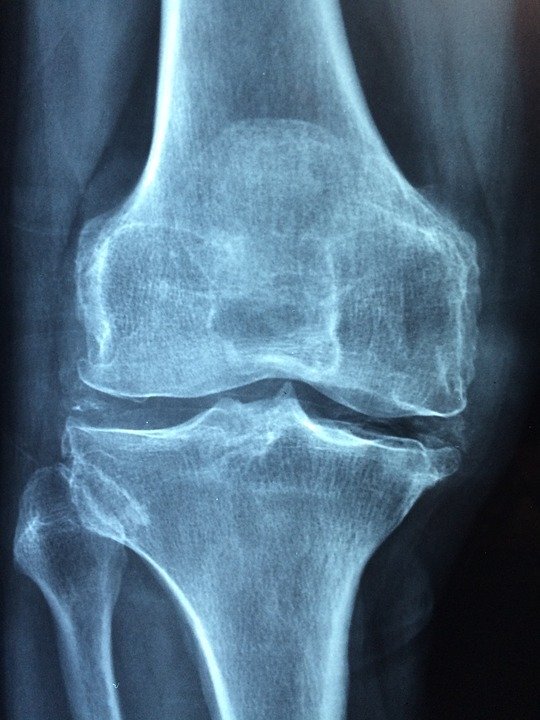

Суставы - это подвижные соединения костей, покрытые суставной сумкой, внутри которой находится синовиальная (смазывающая) жидкость.

Суставы наших ног подвержены влиянию нашего тела, неправильным движениям. Суставы очень быстро изнашиваются. При этом ещё существует еда, которая ускоряет этот процесс.